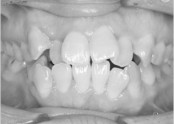

• 치아교정 덧니 교정

• 36